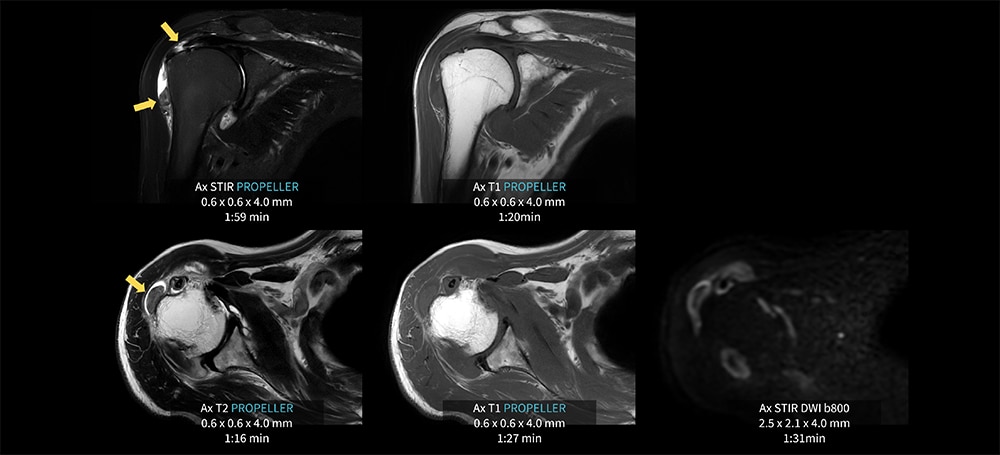

Case8 PROPELLER/変形性肩関節症

80代、男性。変形性肩関節症にてMRI検査を施行した。

関節液の貯留が見られ、棘上筋腱周囲にSTIR像にて高信号域が見られる。上腕骨骨頭外側では、貯留関節液内に10㎜大の低信号域を認め遊離体を疑う。AIR Recon DL併用のPROPELLERにより痛みや呼吸による肩関節周囲の動きの抑制が可能となり、各シーケンス1分台の短時間撮像を実現している。各シーケンスの短時間化のため発生した余剰時間にて、拡散強調像を追加し情報量を高めている。

図8 PROPELLER を用いた肩関節検査